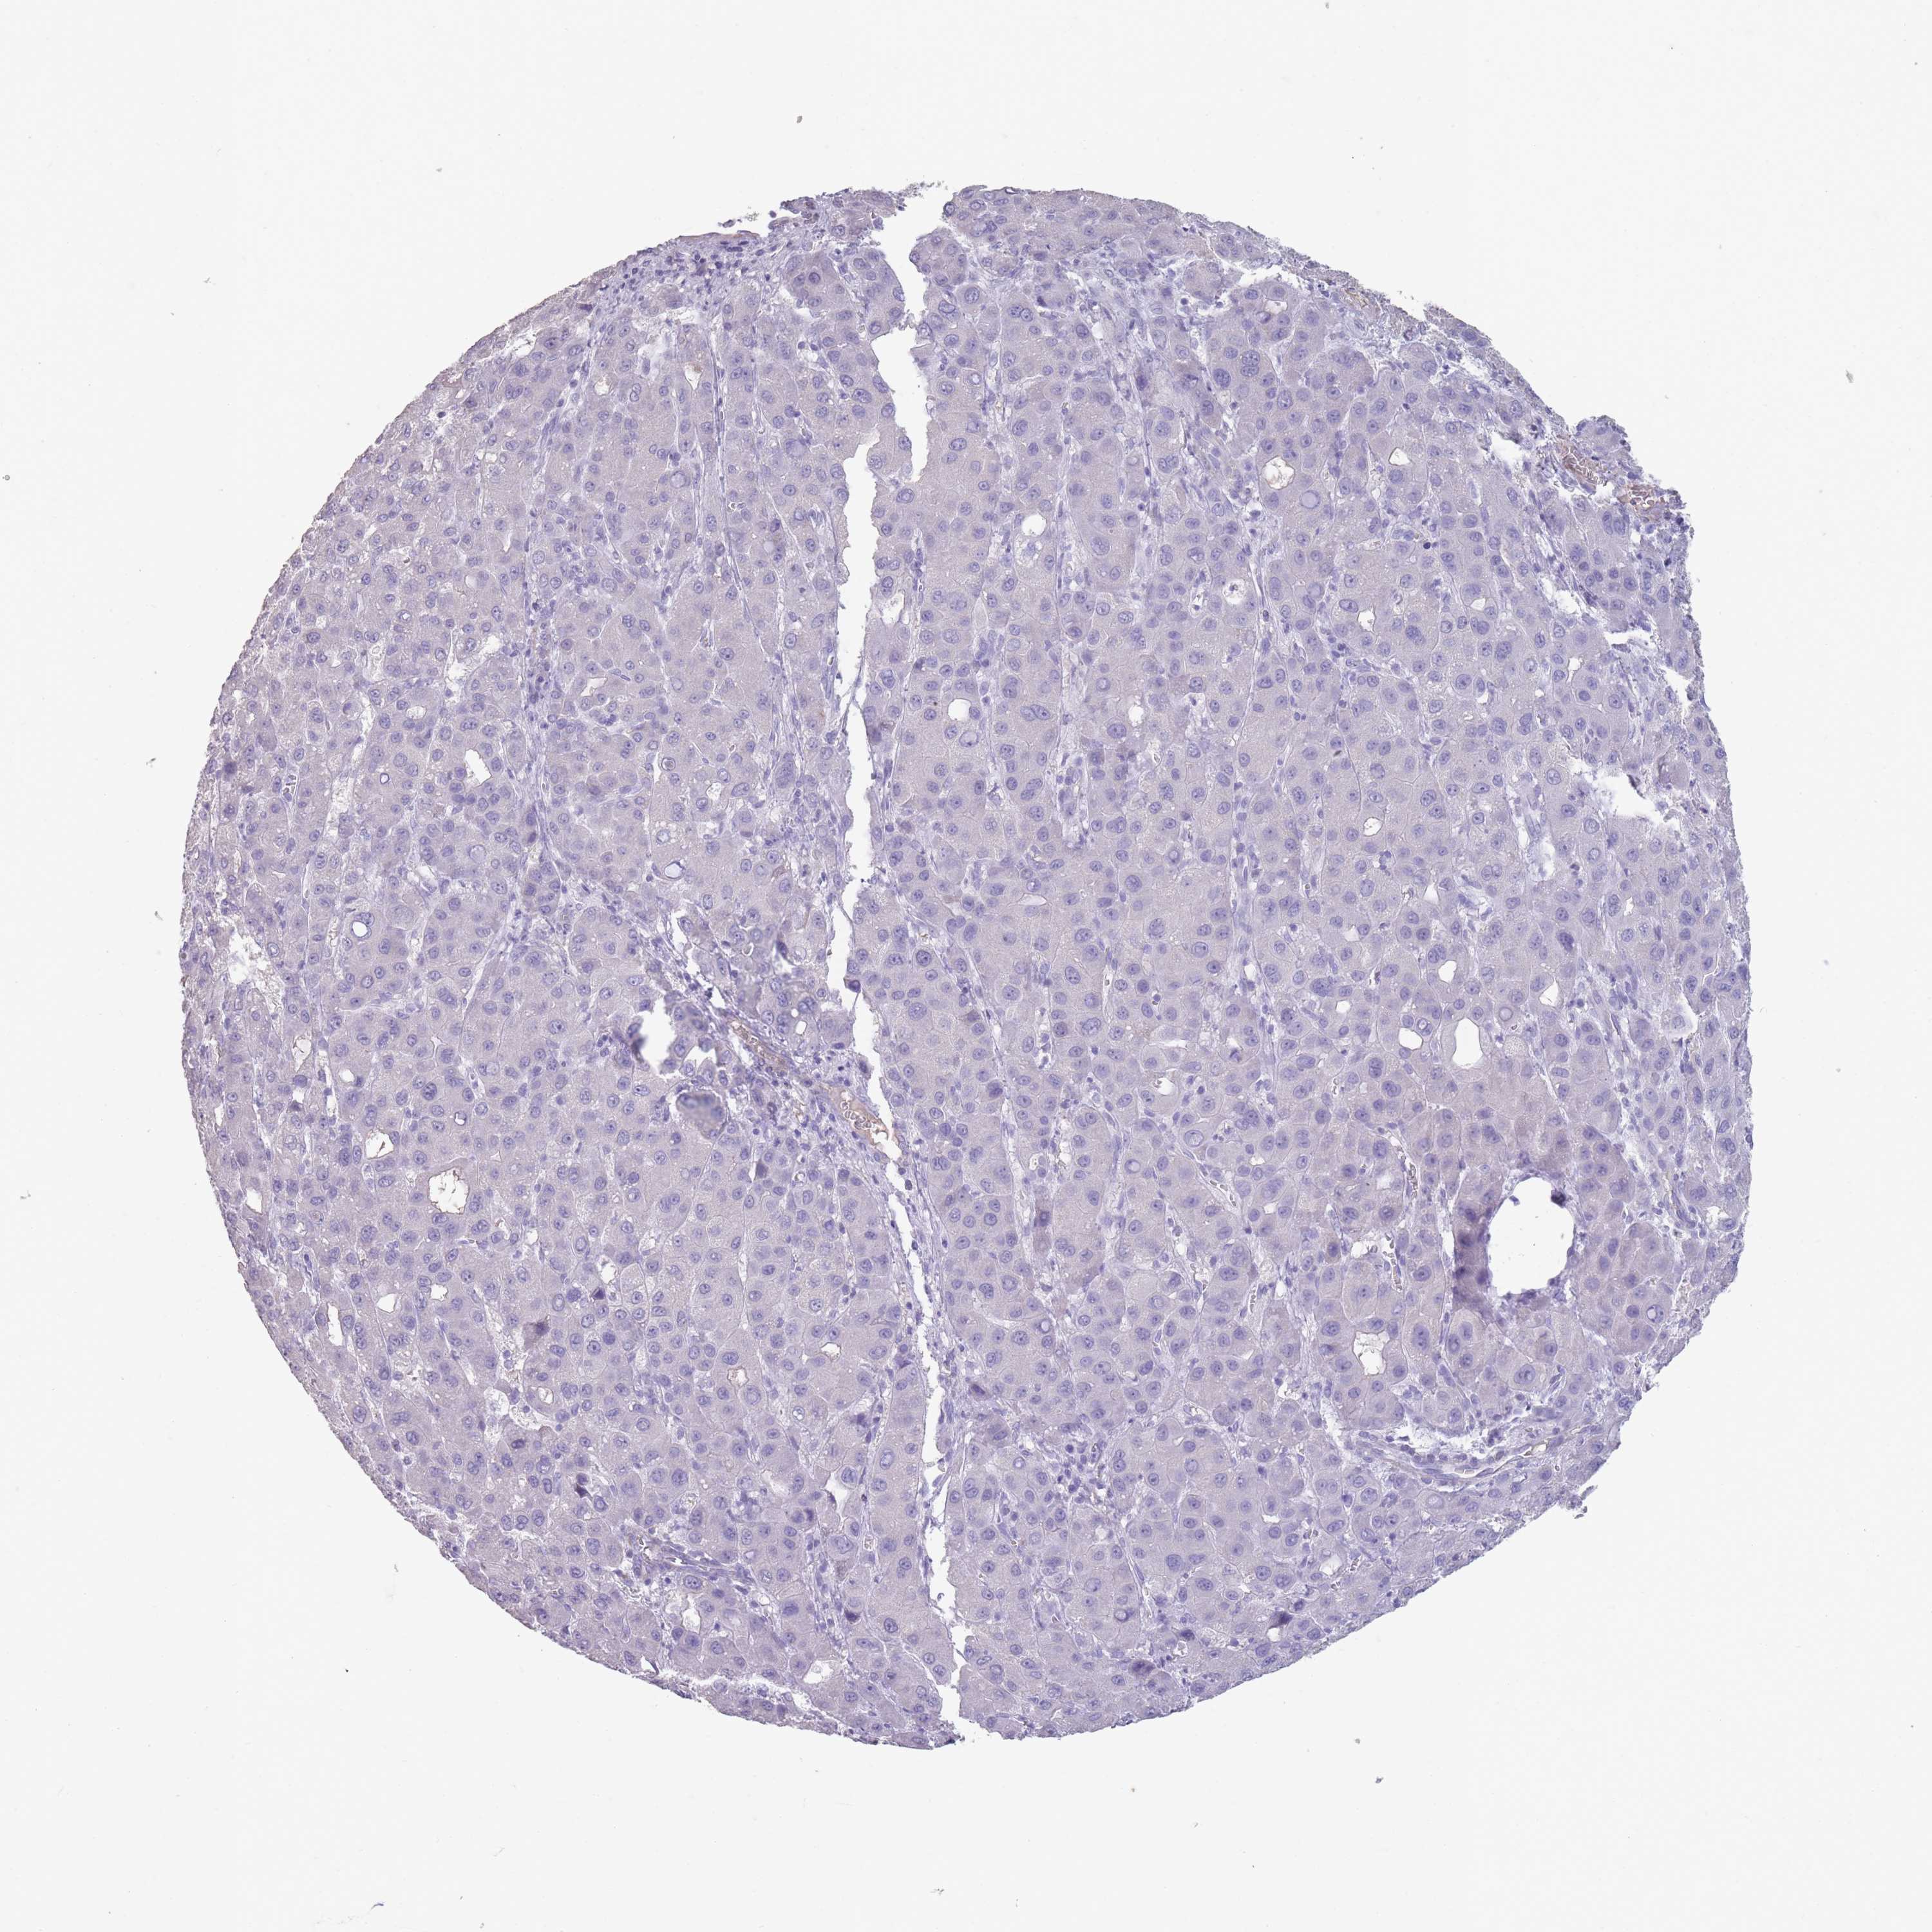

LIVER CANCER - Protein expressioni

A mouse-over function shows sample information and annotation data. Click on an image to view it in a full screen mode. Samples can be filtered based on level of antibody staining by selecting one or several of the following categories: high, medium, low and not detected. The assay and annotation is described here.

Note that samples used for immunohistochemistry by the Human Protein Atlas do not correspond to samples in the TCGA dataset.

Antibody stainingi

Antibody staining in the annotated cell types in the current human tissue is reported as not detected, low, medium, or high, based on conventional immunohistochemistry profiling in selected tissues. This score is based on the combination of the staining intensity and fraction of stained cells.

Each image is clickable and will lead to virtual microscopy that enables deeper exploration of all samples and also displays staining intensity scores, fraction scores and subcellular localization as well as patient and tissue information for each sample.

Antibody HPA048489

Staining

High

Medium

Low

Not detected

Intensity

Strong

Moderate

Weak

Negative

Quantity

>75%

75%-25%

<25%

None

Location

Nuclear

Cytoplasmic/membranous

Cytoplasmic/membranous,nuclear

Cholangiocarcinoma

Carcinoma, Hepatocellular, NOS